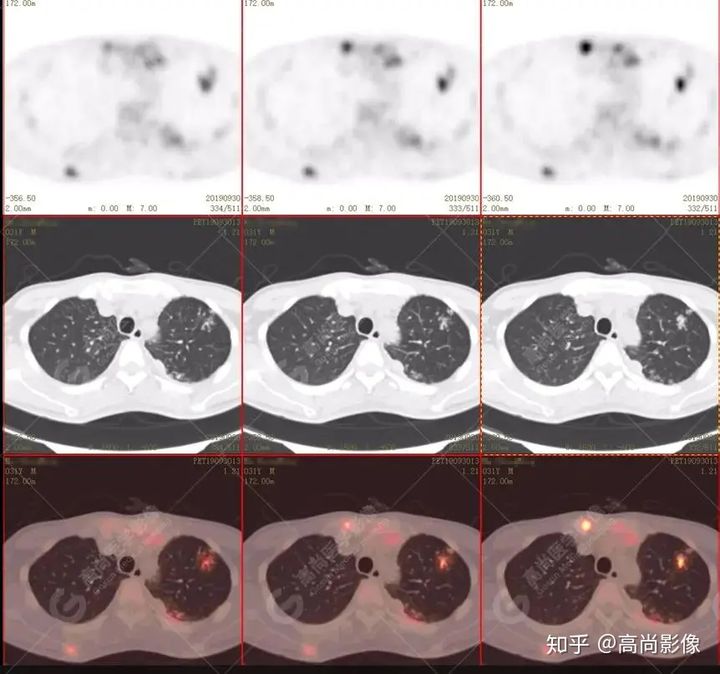

左肺上葉尖后段及下葉背段多發(fā)簇狀斑點(diǎn)狀高代謝灶

左側(cè)胸膜結(jié)節(jié)樣增厚,代謝不同程度增高

【PET/CT提示】雙肺、左側(cè)胸膜多發(fā)結(jié)節(jié)影,全身多處骨質(zhì)破壞,全身多發(fā)淋巴結(jié)腫大,代謝攝取不均勻性增高。